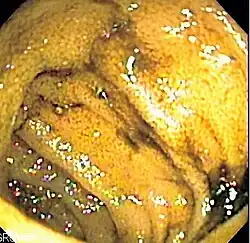

![]() Endoscopic image of normal small bowel | |